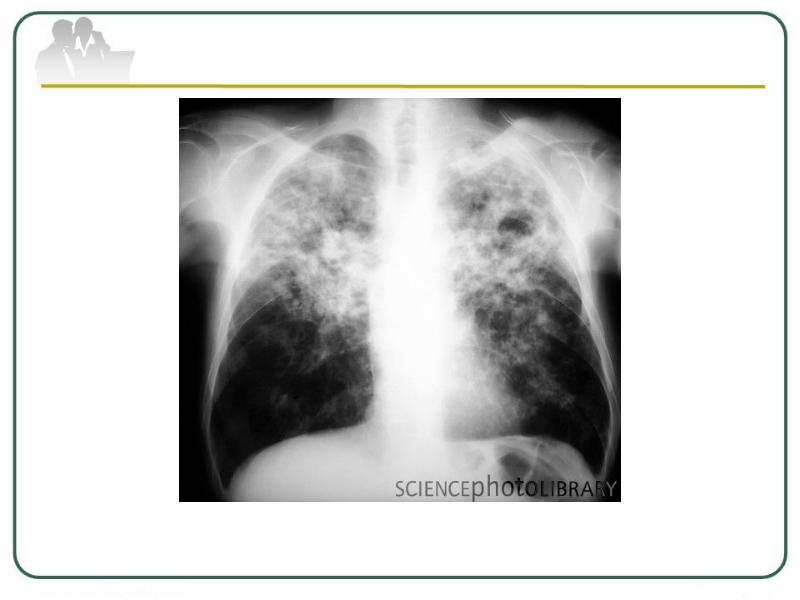

Очаговый и инфильтративный туберкулез презентация - 94 фото